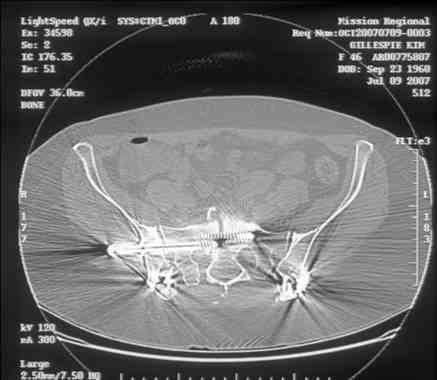

[Ortho] Sacral Non-Union

----------- следущая часть -----------

Вложение не в текстовом формате было извлечено…

Имя     : slide0003_image006.jpg